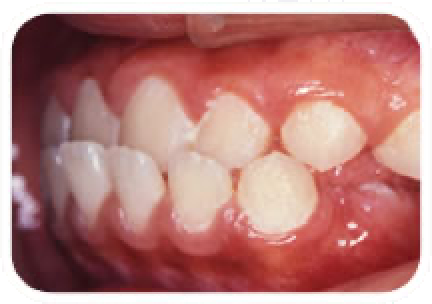

出っ歯(上顎前突)

上の前歯が前方にとびだしている状態です。原因としては色々ありますが、小さい頃の指しゃぶりが長く続くとこのような状態になる場合があります。このまま放置しておきますとますます出っ歯がひどくなる場合もあります。